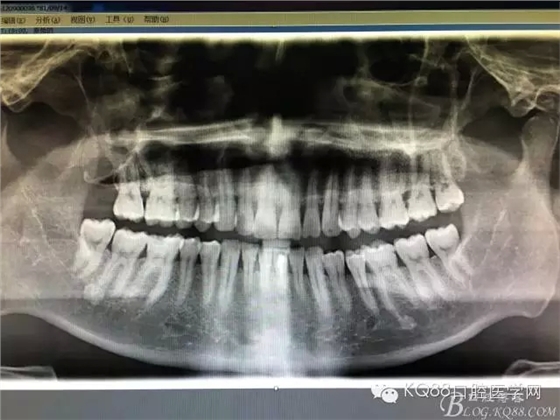

圖2.術(shù)前做全景片影像檢查:18頰舌向高位阻生,牙冠位于17牙根的正上方,懷疑18位于上頜竇內(nèi)。

圖18.術(shù)后的全景片影像檢查:

圖19.局部放大影像檢查:17牙根未見損傷